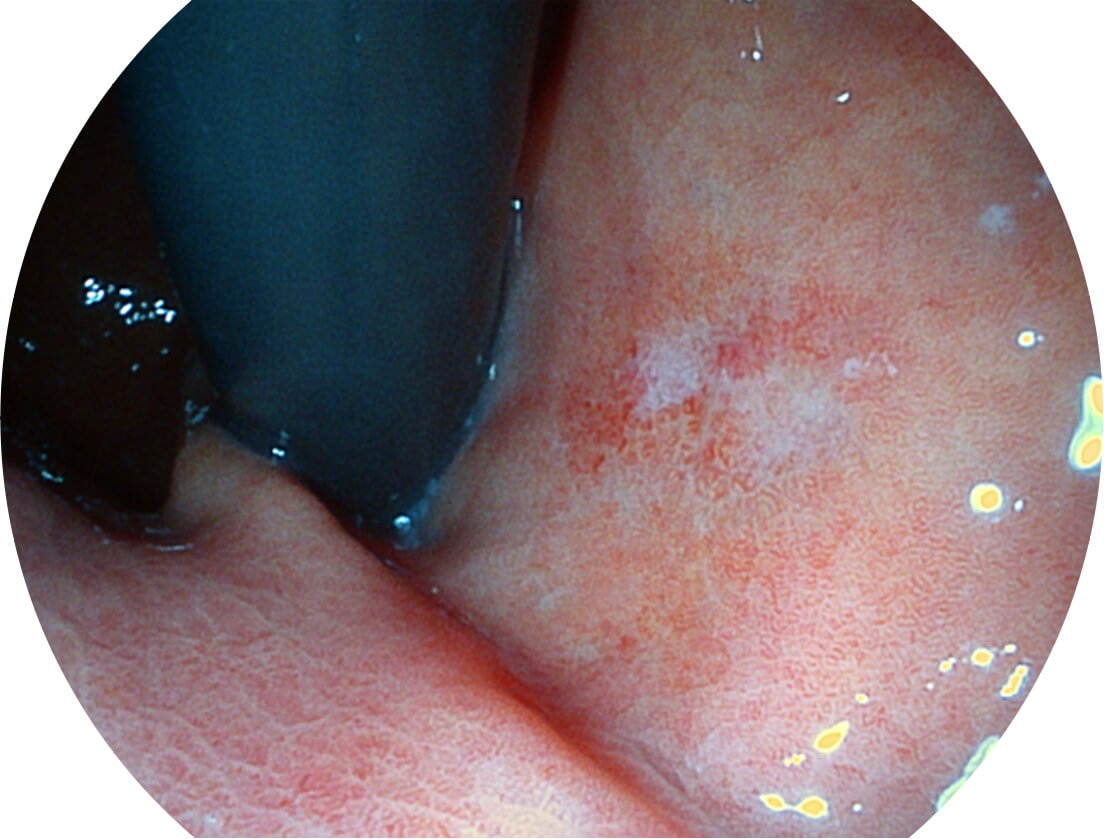

强调浅层黏膜结构的同时,保证照明亮度和提升浅层微血管与中层血管颜色对比度,病变边界更清晰。

白光图像

VIST图像